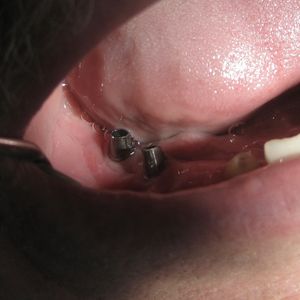

Surgical placement: the implant is inserted into the jawbone under local anaesthesia. The procedure is minimally invasive and typically painless.

Prosthetic rehabilitation: once osseointegration is complete, an abutment and permanent crown, bridge, or denture is placed on the implant. Prosthetic rehabilitation on implants is our core specialty and is key to the long-term success of the treatment.